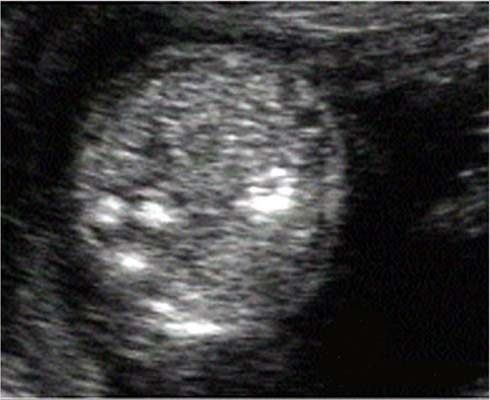

Des calcifications parenchymateuses périventriculaires doivent être recherchées ; celles ci peuvent être isolées. Plus exceptionnellement, une atteinte ischémique peut se traduire par une porencéphalie, une encéphalomalacie multikystique ou une hydranencéphalie.

La séméiologie échographique décrite par les différents auteurs comporte les signes suivants :